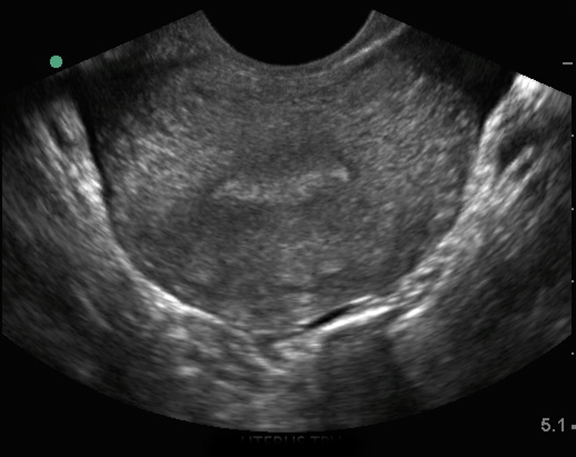

骨盤の経膣子宮: 子宮横 1 画像

子宮横行